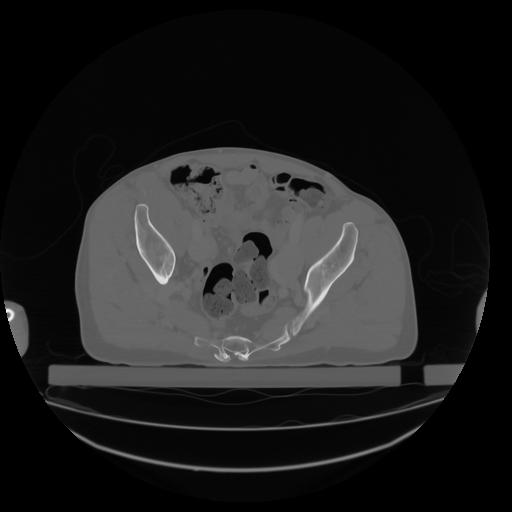

27 CUERPO,CE,Axial,3.0,CUERPO,,